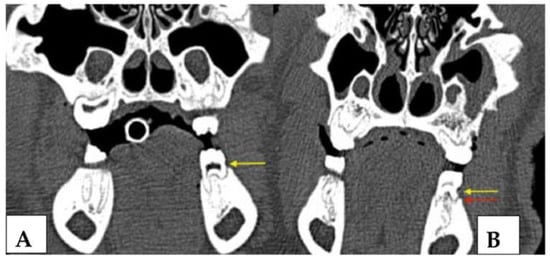

3.2.3. Radiological Evaluation